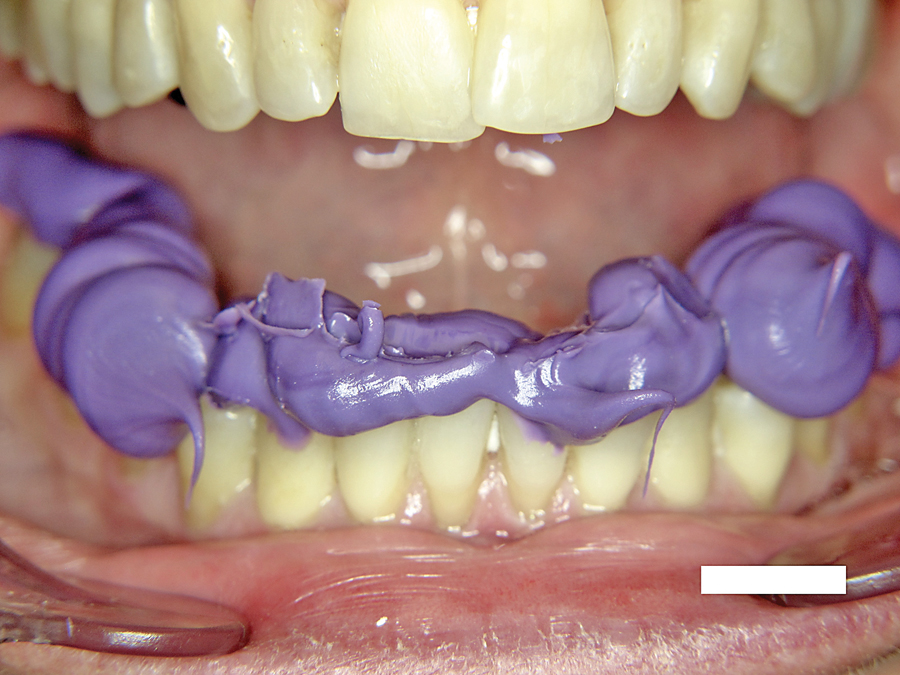

Mastering The Art Of Impression Making

INTRODUCTION: MASTERFUL FINAL IMPRESSIONSThe excellence and marginal fit of the definitive laboratory restorations can only be as good as the master dies from which they are created. The precision of the master impression is something that cannot be compromised. We often think of this procedure as “basic”, but dental laboratories will many times report that … Read more